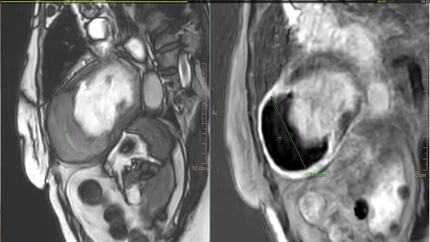

Acute coronary syndrome with mechanical complication and long-term sequelae.